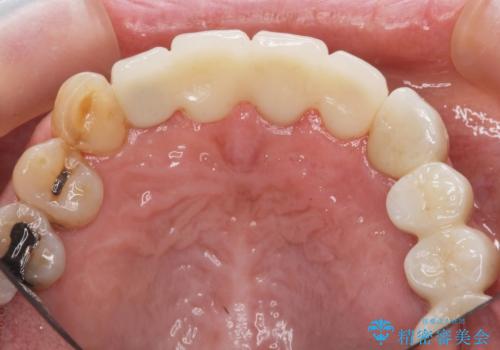

3. ぐらつく前歯 ブリッジ治療の治療後